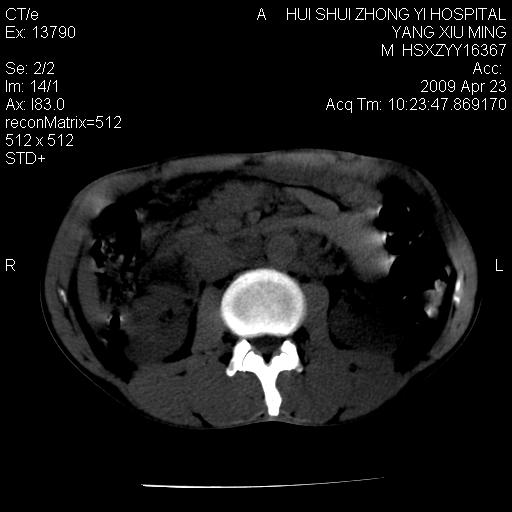

上腹部疼痛一月,呕吐10天,发现左侧颈部包快10天 胸部cr片未见明显异常。

腹膜后淋巴结增大,转移、淋巴瘤?胰腺增大,胰腺炎?占位?颈部考虑增大淋巴结。建议腹部增强扫描。

黑!广泛淋巴结肿大不符合胰腺癌转移。胰腺周围淋巴结肿大致使胰腺看起来大。考虑淋巴瘤可能大。

颈部及腹膜后淋巴瘤可能性大